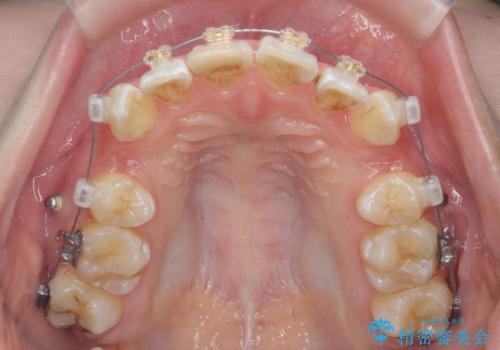

突き出た前歯を治したい 小臼歯抜歯+マルチブラケット矯正

- 矯正装置

- ワイヤー矯正

- 治療期間

- 2年8ヶ月

- 突き出て、気になる前歯の角度の改善を求めて来院されました。

前歯の角度を改善するために小臼歯4本の抜歯を行いワイヤー マルチブラケットを用いて、しっかりと前歯の角度を改善する治療計画としました。

綺麗な歯並びを手に入れられたと同時に、口元もスッキリし、仕上がりに満足いただくことができました。